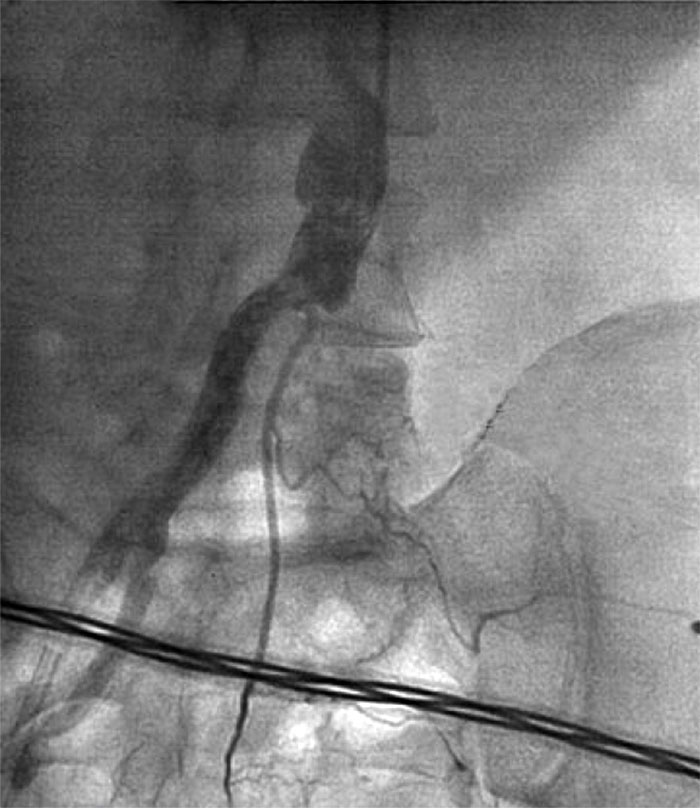

LCA trunk stenting was performed, antegrade blood flow — TIMI 3. The patient was transferred to the intensive care unit (ICU) for treatment with high doses of adrenergic agonists and intra-aortic balloon counterpulsation (IABC) 1:1. Within 90 minutes, the patient was transferred to the operating room for angiography of the left lower limb, as he had significant pain in the left leg without effect from opioids, and he had no pulsation over the popliteal artery and the dorsal pedis artery. Angiography showed thrombotic occlusion of the left common iliac artery.

Fig. 2. Left iliac artery occlusion